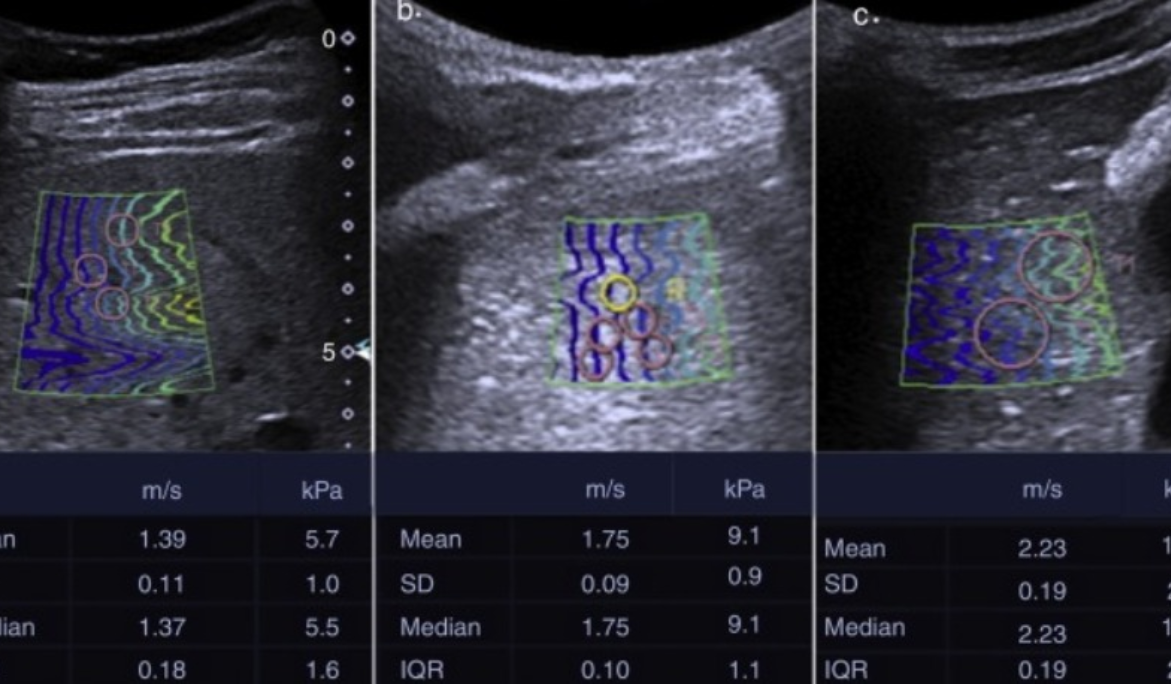

Las elastografía utiliza vibraciones de baja frecuencia durante un ultrasonido o una RMN para medir la rigidez (o elasticidad) de órganos internos. Es particularmente útil para detectar la presencia y la gravedad de enfermedades del hígado. Con un procedimiento de elastografía es posible detectar el grado de fibrosis y cirrosis del hígado.. En el proceso, la cabeza sónica envía una onda de baja frecuencia dentro del tejido hepático cuya velocidad de propagación se mide por medio del ultrasonido. Cuanto mayor sea la velocidad de propagación, más alto es el grado de fibrosis. Un método similar para determinar el grado de elasticidad es la elastografía por ondas de corte, la cual se ha integrado en dispositivos de ultrasonido de rutina.

Este método posee ventajas potenciales sobre los métodos actuales, suministrando un cuadro más amplio y completo de la enfermedad hepática y también puede revelar otros tipos de lesión hepática. Es una pruebas no invasiva, respecto a la biopsia, resultando más cómoda para el paciente y permitiendo al mismo tiempo hacer un seguimiento frecuente cuando sea necesario.